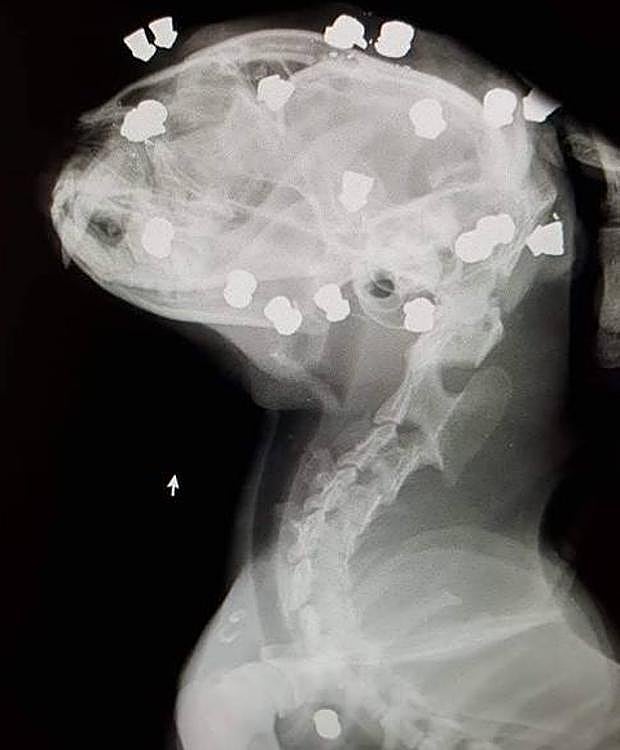

Aparece un gato con 18 perdigonadas en Lardero

La Coordinadora por el Sacrificio Cero de La Rioja ha denunciado el hallazgo en Lardero de un gato con 18 perdigones incrustados en su cabeza.

En este caso «grave de maltrato y violencia a los animales» el gato había sido víctima de disparos hechos con carabina, de uno en uno, por lo que el animal debía de estar confinado en algún sitio sin escapatoria mientras el autor de los hechos se ensañaba con él.

Afortunadamente el animal se encuentra estable y en buenas condiciones, a excepción de la alta probabilidad de que pierda un ojo debido a uno de los disparos, explican.